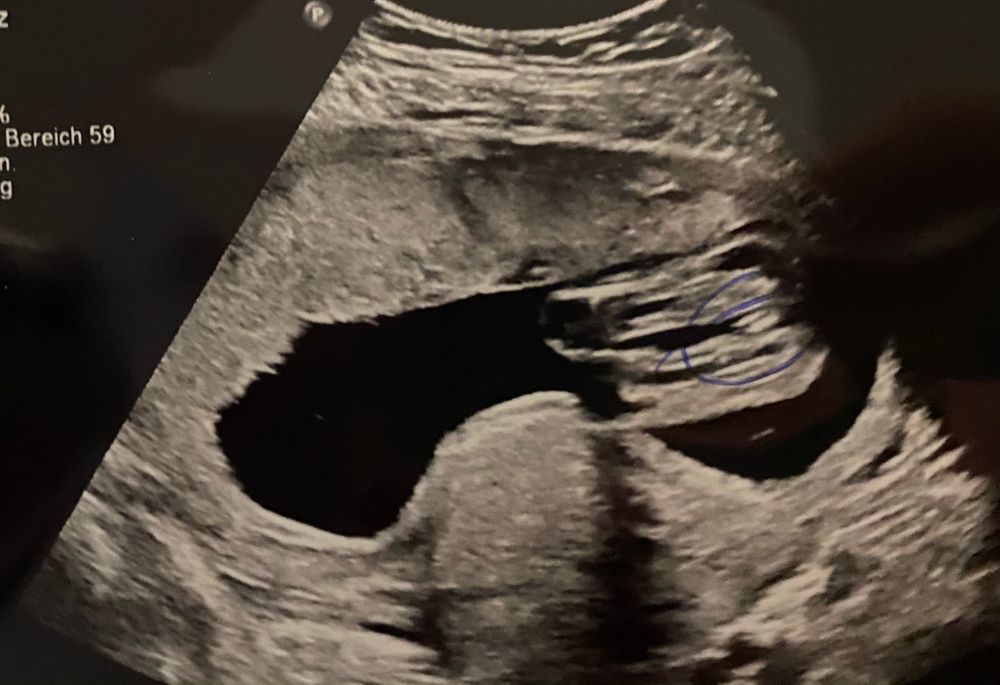

УЗИ, КТГ, доплер18 недель .

Вот на первой фотке вижу пирожок,а на второй бугорок 🤷♀️ Это обе фотки между ножек.

Вес -230 грамм,рост 18 см. Лежит поперёк,я и чувствую удары ножкой всегда слева. Вот и сама ножка ,2.30 см😂